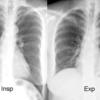

Insp & Exp

Ex 1

Date: 03/24/2004

Views: 5613